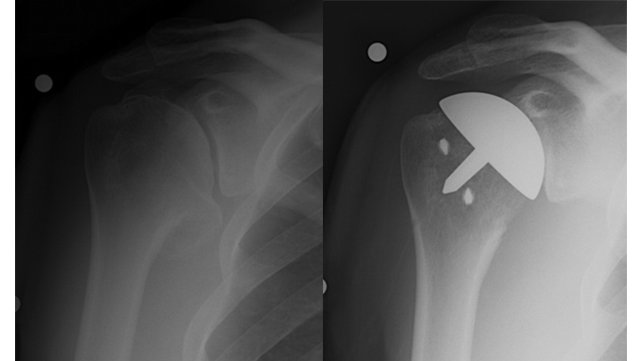

X-rays of pre- and post-operative humeral resurfacing

Pre- and Post-Operative Resurfacing

(Fig. 5) X-rays of an active, 40-year-old man with shoulder arthritis who was treated with humeral head resurfacing.